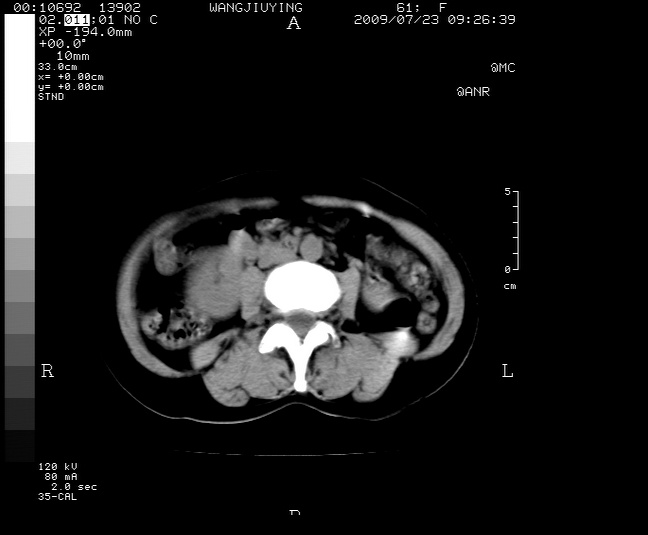

以下是引用卜一在2009-7-24 6:56:00的发言:[br]定位:肾包膜下!性质难定:血肿肌化?慢性脓肿钙化?建议手术切除!

以下是引用为了春天在2009-8-12 21:10:00的发言:[br]ct21255 镜检:部分肾组织分化可,由肾小球及肾小管构成,肾囊壁大片坏死及钙化,未见类上皮细胞,朗汗巨细胞》。 诊断:肾囊肿伴大片坏死钙化,结核不能排外。

以下是引用王仕学在2009-7-24 8:33:00的发言:[br]考虑囊肿、囊壁钙化。